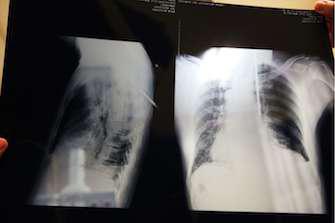

Le premier essai a inclus 272 patients atteints de cancer du poumon non à petites cellules épidermoïde et présentant des métastases. La moitié des participants a reçu le traitement de référence dans cette maladie, du docétaxel. L’autre moitié a bénéficié de l’immunothérapie Opdivo, jusqu’ici autorisée dans le mélanome de stade métastatique.